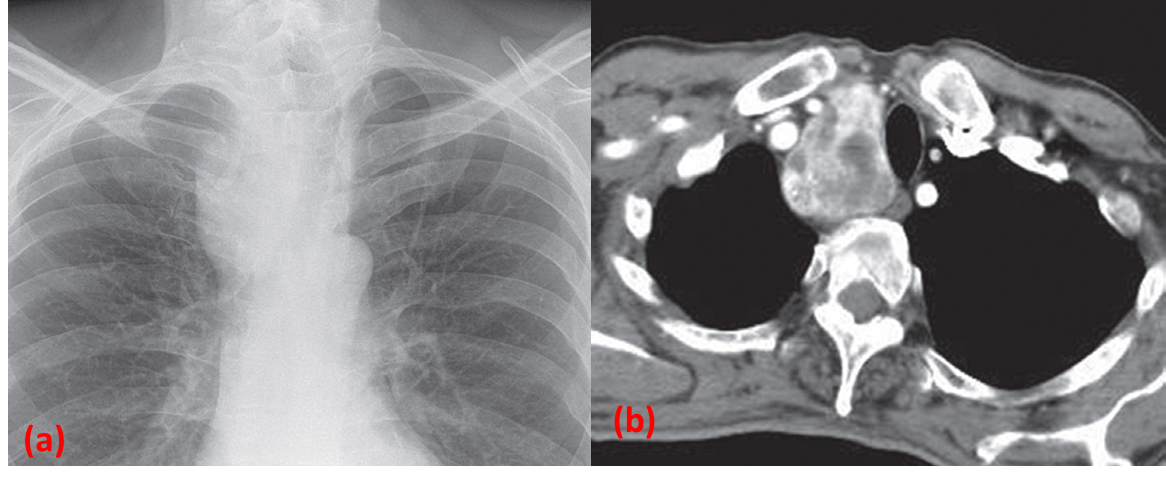

Retrosternal goitre.

(a) X-Ray showing a large, right-sided, superior mediastinal mass displacing the trachea.

(b) CT in the same patient showing the heterogeneously enhancing mass to the right of the trachea